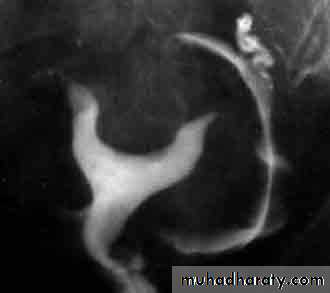

HSG : RT corner is blocked

HSG showing a normal uterus and blocked tubes No "spill" of dye is seen at the ends of the tubes Both tubes are slightly dilated and fluid filled - hydrosalpinxHSG : fibroid is pushing in to the uterus cavity